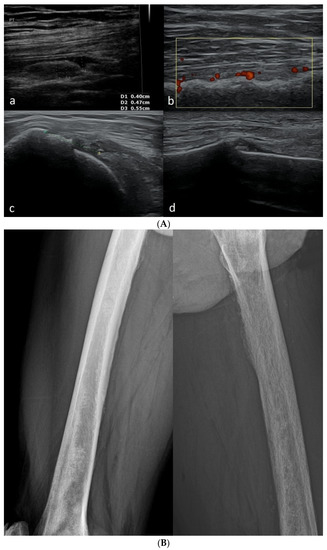

Basic Differences and Most Common Findings in Ultrasound Examinations of Musculoskeletal System in Children: A Narrative Literature Review

by Tomasz Poboży, Wojciech Konarski, Karolina Piotrowska-Lis, Julia Domańska, Kamil Poboży and Maciej Kielar

Healthcare 2022, 10(10), 2010; https://doi.org/10.3390/healthcare10102010 - 12 Oct 2022

We present basic differences in the musculoskeletal ultrasound examinations between adults and children. Examiners who deal with adults on a daily basis have shared concerns about examining children. Such concerns may arise from the different approach to child ultrasounds, but they also come [...] Read more.

We present basic differences in the musculoskeletal ultrasound examinations between adults and children. Examiners who deal with adults on a daily basis have shared concerns about examining children. Such concerns may arise from the different approach to child ultrasounds, but they also come from differences in anatomical characteristics according to developmental age. We discuss the presence of growth plates, as well as non-mineralized parts of the bones. We also refer to the pathologies most often found in ultrasounds in early developmental stages. In the PubMed database, the set of keywords: “msk ultrasound in children”, “pediatric msk sonoanatomy”, “coxitis fugax”, “pediatric Baker’s cyst”, “Baker’s cyst ultrasonography”, “bone septic necrosis in ultrasonography”, “ultrasonography in juvenile idiopathic arthritis”, and “ultrasonography in juvenile spondyloarthropathies”, was used to identify a total of 1657 results, from which 54 was selected to be included in the article. We discuss the problem of osteochondritis dissecans, Osgood-Schlatter disease, examples of ligament injuries (especially in relation to the knee and ankle joints), exfoliation of growth cartilages, osteochondroma, exudates and inflammations affecting joints, and Baker’s cysts. In this way, we have collected useful information about the most common diseases of the musculoskeletal system in children. Full article

Show Figures

Figure 1